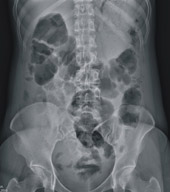

常見便秘的症狀及徵候如下:腹部的膨脹感、腹痛、腸脹氣,而且在排便之後才能得到緩解。便秘一旦慢性化,大腸內堆積的代謝廢物會導致沒有精神、噁心、嘔吐、口臭、食欲不振。當患者抱怨有便秘的情形,必須包括排便次數、糞便的型態、是否合併其他症狀或徵候等有意義的內容。診斷所需要的資訊如下:過去的臨床病史、藥物史、排便日記、評估便秘的等級、評估便秘、腹瀉的等級、記載糞便型態的等級、症狀與徵候的等級。大部分的便秘情形,只要評估病史加上簡單的身體檢查就可以正確的掌握病因及嚴重度,並確立治療方式。有時狀況不確定或症狀有變化時,會視情況安排進一步檢查,通常最簡便的是腹部X光檢查(圖一),可直接發現腸氣分佈與糞便堆積情形。此外,腸道構造上是否異常,也常常是老人便秘需考慮的重要原因,例如大腸是否長腫瘤或狹窄,然後再安排內視鏡(圖二)或者大腸鋇劑攝影,以尋找大腸內是否有憩室、息肉、或腫瘤等構造上的問題。此外,甲狀腺功能、血中電解質濃度、牙科檢查、神經學檢查等等也都能幫助診斷。

圖一.腸氣分佈情形